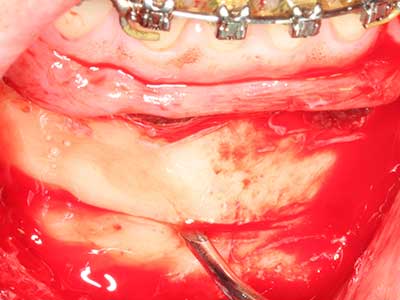

Piezo surgery has additional advantages when harvesting bone blocks. In addition to the high precision with osteotomy described above, the use of the thin saw tips specifically minimizes loss of material. Greater loss of material during harvesting can be expected with the thicker instrument tips, particularly when using Lindemann drills (Lakshmiganthan, Gokulanathan et al. 2012). The basal separation, which is necessary particularly for retromolar block transplants, is simplified by specially designed rectangular saws, with the result that piezo surgery is viewed as a precise, simple and safe procedure for harvesting retromolar bone blocks (Happe 2007) (Fig. 1-12).

The splitting procedure is particularly atraumatic and there is no significant loss of dimension when using piezosaws, and there are no significant differences between implants in split jaws and implants in an alveolar ridge without a bone deficit (Chiapasco, Zaniboni et al. 2006, Danza, Guidi et al. 2009). However, sufficient continuous irrigation is essential, particularly with locally restricted and deep splitting to prevent thermal stress in the apical osteotomy regions.